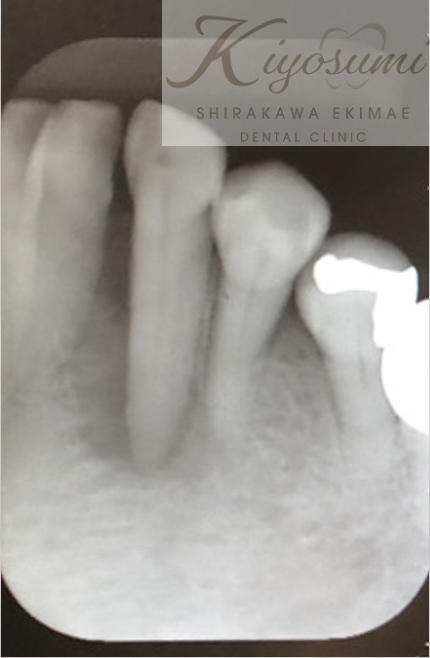

| 主訴 | 歯が揺れて噛めないので、噛めるようにして欲しい。 |

| 治療内容 | 基本的な歯周病治療、根の治療を実施し、歯の高さが足りない箇所は歯冠長延長術、保存が難しい歯は一部歯根分割抜去を行いました。欠損部はインプラントを用いず、ジルコニアブリッジで仕上げています。 |

| 想定されたリスク | ※残存している歯の本数が少ないため、残っている歯だけでブリッジを行うには長期予後が見込めない可能性があり、患者さんにご理解をいただいたうえで被せ物を行っています。 ※歯周病治療や根の治療をしても歯を残せない可能性がありました。 |